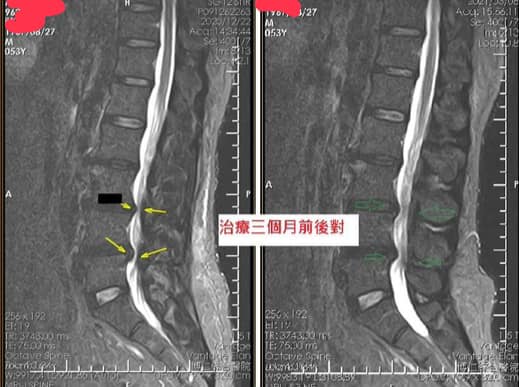

Cervical Spine Treatment Cases 腰椎治療案例 #巨大椎間盤突出一定要開刀嗎? #兩家醫學中心外科醫師說很嚴重! #有沒有辦法逆轉勝... 2021.08.10 ❖ 椎間盤突出治療醫案 ❖晨起痛爆整個人無法工作心情沮喪 😂骨科醫師說復健如果沒效可... 2022.05.12 #天才年輕賽車手巨大椎間盤突出醫案 #八周治療完全逆轉勝康復 #重新回到合法賽車場競... 2021.07.20 #腰椎滑脫痛苦不堪 #右腳麻痛無法彎腰刷牙 #感謝桃園市楊小姐熱情見證 #患者親自贈送... 2021.06.15 #巨大椎間盤突出醫案 #真的逆轉勝超感動 #三個月治療完全徹底改善 #脊刻救援成功 #徹... 2021.06.12 ⭕️L4L5巨大椎間盤突出治療醫案 🌟八週之內解除危機逆轉成功 😁順利降級成功解封印 💪... 2021.07.08 #腰椎多節椎管狹窄治療醫案 #腎臟病患者可接受中醫微創筋膜療嗎? #感謝台北市信義區張... 2021.06.01 #腰椎手術失敗綜合症候群 #感謝桃園呂伯伯熱情見證 #何時必須優先考慮再次動刀 #脊刻... 2021.07.31 #感謝新店吳先生熱情見證 #車禍後導致椎間盤突出醫案 #傳統復健六周無效痛苦不堪 #脊... 2021.05.29 #椎間盤突出治療醫案 #破紀錄三週解決 #真的逆轉勝 #感謝新莊周先生熱情見證 #脊椎整... 2021.05.26 #脊椎滑脫合併椎管狹窄醫案 #感謝台北市曹阿姨熱情見證 #之前大痛到無法走路只能拐杖... 2021.05.14 #嚴重椎管狹窄醫案導致寸步難行 #最嚴重走路無法超過十公尺 #疼痛到整個人憂鬱到不... 2021.05.07 #巨大椎間盤突出醫案逆轉勝 #感謝台北士林王先生熱情見證 #脊椎整合中醫微創療法 #原... 2021.04.29 #台灣越南國際醫療成功 #脊椎整合中醫微創療法逆轉勝 #腰椎椎間盤突出醫案 #曾經大痛... 2021.04.23 #椎間盤突出逆轉勝醫案 #原本骨科建議開刀 #脊刻救援成功 #感謝雲林患者陳小姐熱情見... 2021.04.09 ← 上一頁 7 8 9 10 11 下一頁 →